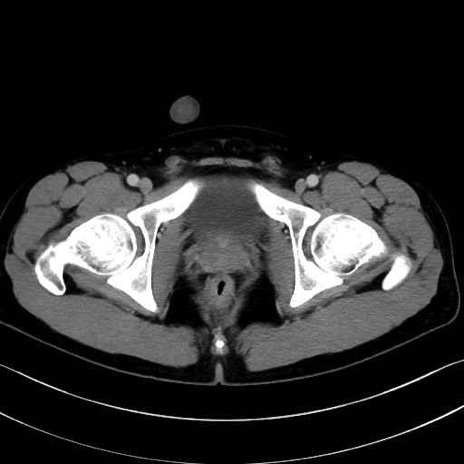

梨状筋(piriformis muscle) のCT画像の解剖

梨状筋 (Piriformis)

内閉鎖筋 (Obturator internus)